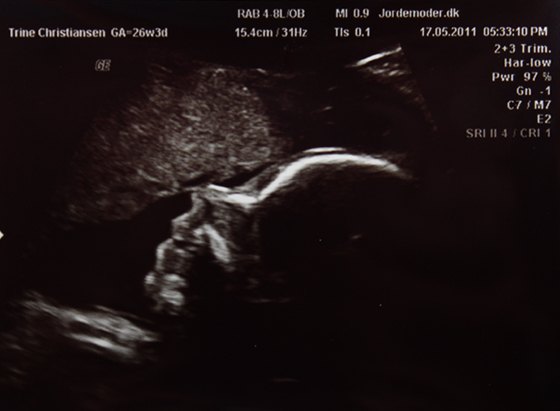

Vi var til en kønscanning i dag

eller lille er måske så eget sagt.. heh.. Der blev selvfølgelig taget lidt forskellig mål og lavet et skøn på vægten, som lyder på Ca. 913g.

Men det hele var bare såå flot. Og så var det jo SUPER dejligt at se Mini T igen

Og her kommer der så et par billeder

To hvor man kan se hovedet og et hvor man kan se kønnet (og det er virkelig ingen tvivl)